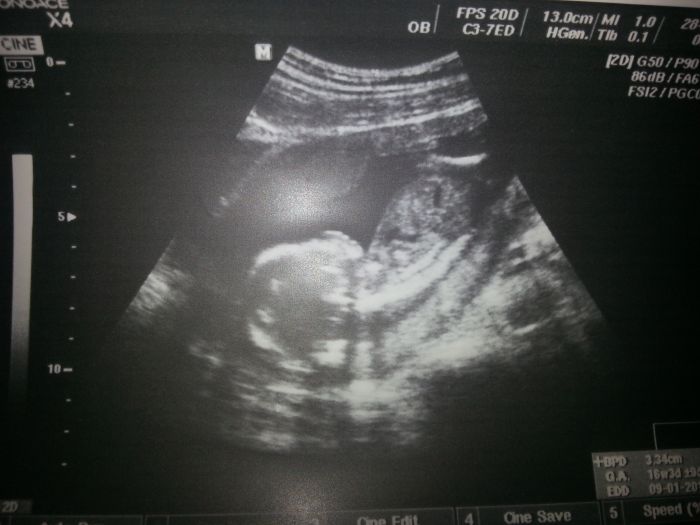

tak ja se taky podelim o naseho mimiska, jen nevime stale co to bude. dalsi kontrolu mam 22.8 tak doufam ze se ukaze ;-D